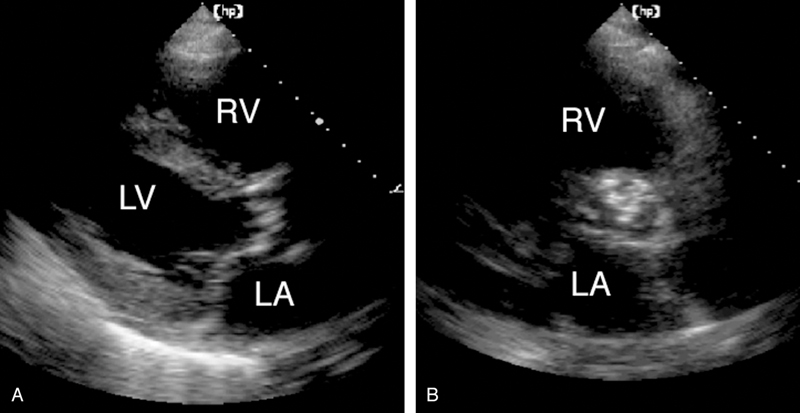

فحوصات تشخيصية لبعض امراض القلب والشرايين التاجية